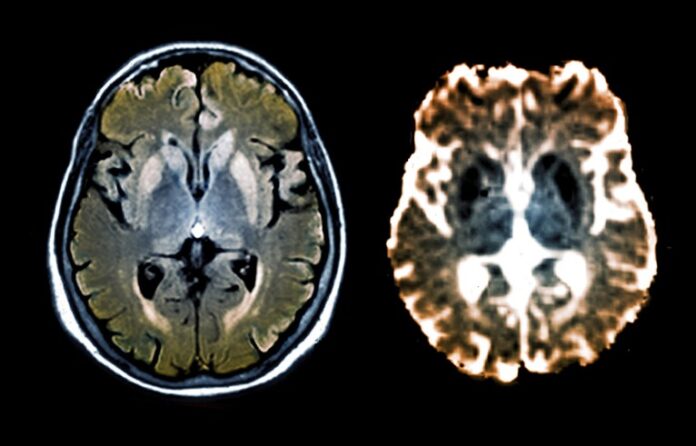

PrP (prion protein) is a protein that naturally exists in brain cells. The development of prion disease is linked to the transformation of normal proteins into a pathological form (PrPSc). In this state, the protein can no longer dissolve in fluid, concentrates in the brain, and causes neuronal degeneration.

In the study, CHARM was successfully tested on mice. Following the injection of CHARM via an AAV vector, scientists observed a 70-90% reduction of PrP protein throughout the brain, which significantly exceeds the results obtained with other methods. The method had no significant side effects. The self-deactivating mechanism ensured that CHARM’s action was controllable and temporary, reducing potential risks and increasing the possibility of future medical use.